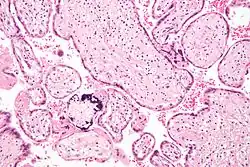

Micrograph of cytomegalovirus (CMV) infection of the placenta (CMV placentitis), a vertically transmitted infection: The characteristic large nucleus of a CMV-infected cell is seen off-centre at the bottom right of the image, H&E stain.

Apart from infecting the fetus, transplacental pathogens may cause placentitis (inflammation of the placenta) and/or chorioamnionitis (inflammation of the fetal membranes).

CMV placentitis